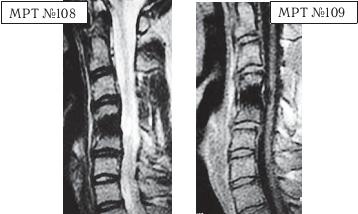

На МРТ № 111 поясничного отдела позвоночника отмечается рецидив — грыжа межпозвонкового диска LIV-LV после трёх операций. Даже если прооперировать в четвёртый раз, то это всё равно не решит проблемы и не добавит здоровья данному пациенту, так как неизбежно возникнут осложнения в вышележащих сегментах LI—LII LIII—LIV в силу биомеханических нарушений в позвоночнике и выраженных дегенеративно-дистрофических изменений в указанных сегментах. На МРТ № 112 поясничного отдела позвоночника отмечается рецидив — секвестрированная грыжа межпозвонкового диска в сегменте LIV-LV после четырёх операций. Здесь, как говорится, без комментариев. К сожалению, в жизни бывает так, что даже профессиональный специалист иногда вместо пользы может принести серьёзный вред пациенту, исключительно из-за шаблонного подхода. Как ни парадоксально это звучит, но это так. Приведу один пример по этому поводу. Ко мне на приём привели женщину. Привели в буквальном смысле этого слова под руки, при этом она ещё дополнительно опиралась на тросточки. Первое о чём я подумал, когда увидел, с какой осторожностью её ведут и как она переставляет ноги, что у данной пациентки как минимум перелом позвоночника с травмой спинного мозга или как максимум — опухоль в спинномозговом канале. Но в данном случае причина оказалось совсем иной. На протяжении последних десяти лет у пациентки периодически возникали боли в поясничном отделе позвоночника. Она к ним привыкла и не переживала по этому поводу, так как боли были умеренные, быстро проходили и довольно легко переносились. Но полтора года назад, после физической нагрузки, появились сильные, тянущие боли в ноге. Женщина вынуждена была обратиться в больницу по месту жительства. Пациентку направили к невропатологу, который, осмотрев её, сделал предположение, что возможно у неё «грыжа межпозвонкового диска» и направил женщину на МРТ. Так вот, сделав МРТ (МРТ №№ 113–115), женщина вернулась со снимками к невропатологу. Он ознакомился с результатами обследования и вместо того чтобы назначить ей консервативные методы лечения при таком диагнозе, направил её… на консультацию к нейрохирургу. Нейрохирург между прочим специалист высокого класса, с большим опытом работы, спасший много человеческих жизней. Однако и он, ознакомившись с результатами обследования, осмотрев пациентку, сделал вывод, что необходима срочная операция по удалению грыжи межпозвонкового диска в сегменте LIV-LV.